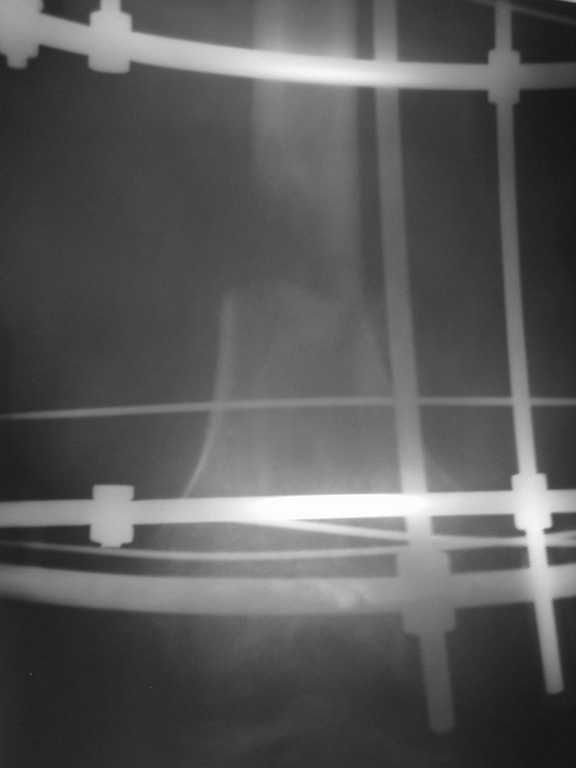

Уважаемые коллеги. Возникли затруднения с выбором оптимальной тактики ведения и лечения больного с огнестерльным ранением правого бедра. Пациент лечился в областной больнице в течении почти двух месяцев, после чего был отправлен на амбулаторное лечение. Травма была получена на Новый Год, прострелили правое бедро сигнальной ракетницей, был многооскольчатый перелом правой бедренной кости, сквозное ранение мягких тканей с обширными ожогами правой и левой конечностей 2 - 3 степени. При поступлении была выполнена ПХО раны, ожогов, наложены асептические повязки. Через две недели наожен аппарат Илизарова для постепенной компрессии отломков. На протяжении 1,5 месяцев проводилась компрессия - в результате отломки стали соприкасаться, укорочение конечности составило примерно 6 см. Рана мягких тканей к этому времени практически закрылась. С этим результатом в начале марта больной был отправлен на амбулаторное лечение по месту жительства (см. рентгеннограммы). Ему были даны рекомендации - продолжить компрессию в течении 6 недель по 1,5 мм в неделю, контрольный снимок через месяц. Пациент следовал рекомендациям,продолжал компрессию и в апреле отослал снимки в областную больницу на консультацию(см. рентгенограммы). Ему посоветовали продолжить компрессию еще на месяц. Последние снимки были сделанны в мае и опять он получил рекомендации продолжать компрессию. После этого он пришел ко мне на консультацию с вопросом - что ему делать. Мое мнение: поскольку наблюдается обширный дефект костной ткани, я бы рекомендовал провести оперативное вмешательство и восплнить этот дефект аллотрансплантантом костной ткани. Трансплантант сыграет роль депо минеральных веществ и заодно ускорит восполнение дефекта. А после этого вторым этапом провести уже удлинение конечности. На ваш взгляд какой тактики лучше придерживаться - продлжать компрессию или провести операцию по восполнению дефекта?

Рентгенограмма от 06.03.2008

2008_03_06_F.jpg